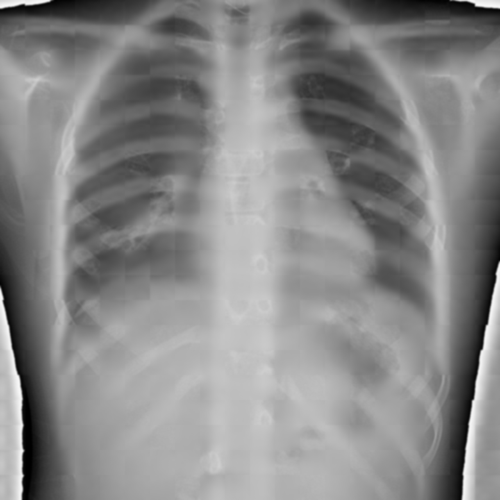

To pre-train a high-performance X-ray foundation model, the first thing we need to do is the collection of large-scale X-ray images. Therefore, a large-scale and high-resolution dataset that contains X-ray medical images is collected for the pre-training. Some representative samples are visualized in Fig. 3.